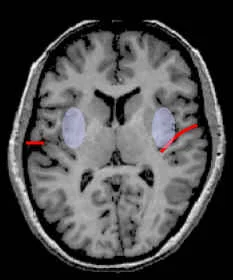

Slice Views

- Central sulcus = red

- Precentral sulcus = green

- Transverse-occipital = purple

- Postcentral sulcus = blue

- Intraparietal sulcus = yellow